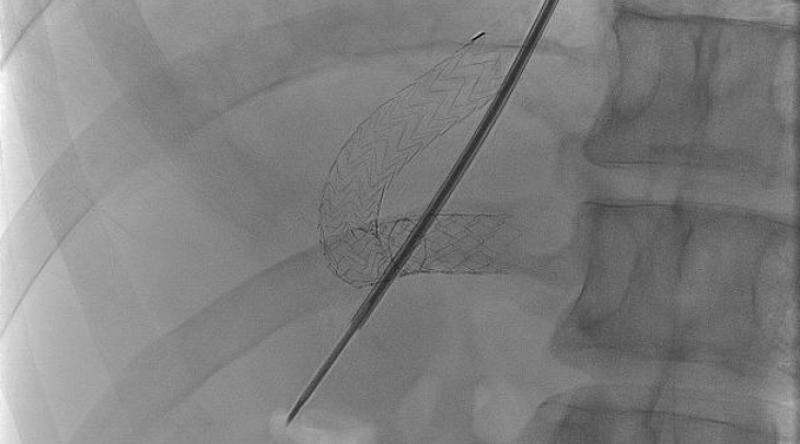

Lebervenenverschlussdruckmessung und Transjuguläre Leberbiopsie

Der Lebervenenverschlussdruck (HVPG) ist der Goldstandard in der Erfassung der portalen Hypertension. Unter anderem ist er ein wichtiger prognostischer Faktor für das Überleben bei Leberzirrhosepatienten und ein wichtiger Parameter zur Beurteilung des Blutungsrisikos von Ösophagusvarizen.

Eine Leberbiopsie ist der Goldstandard in der Diagnostik von Lebererkrankungen. Allerdings kann es zu schweren Komplikationen bei bestimmten Vorerkrankungen kommen. Eine transjuguläre Leberbiopsie (ohne Perforation der Leberkapsel) stellt für diese Patienten eine sichere Alternative dar.